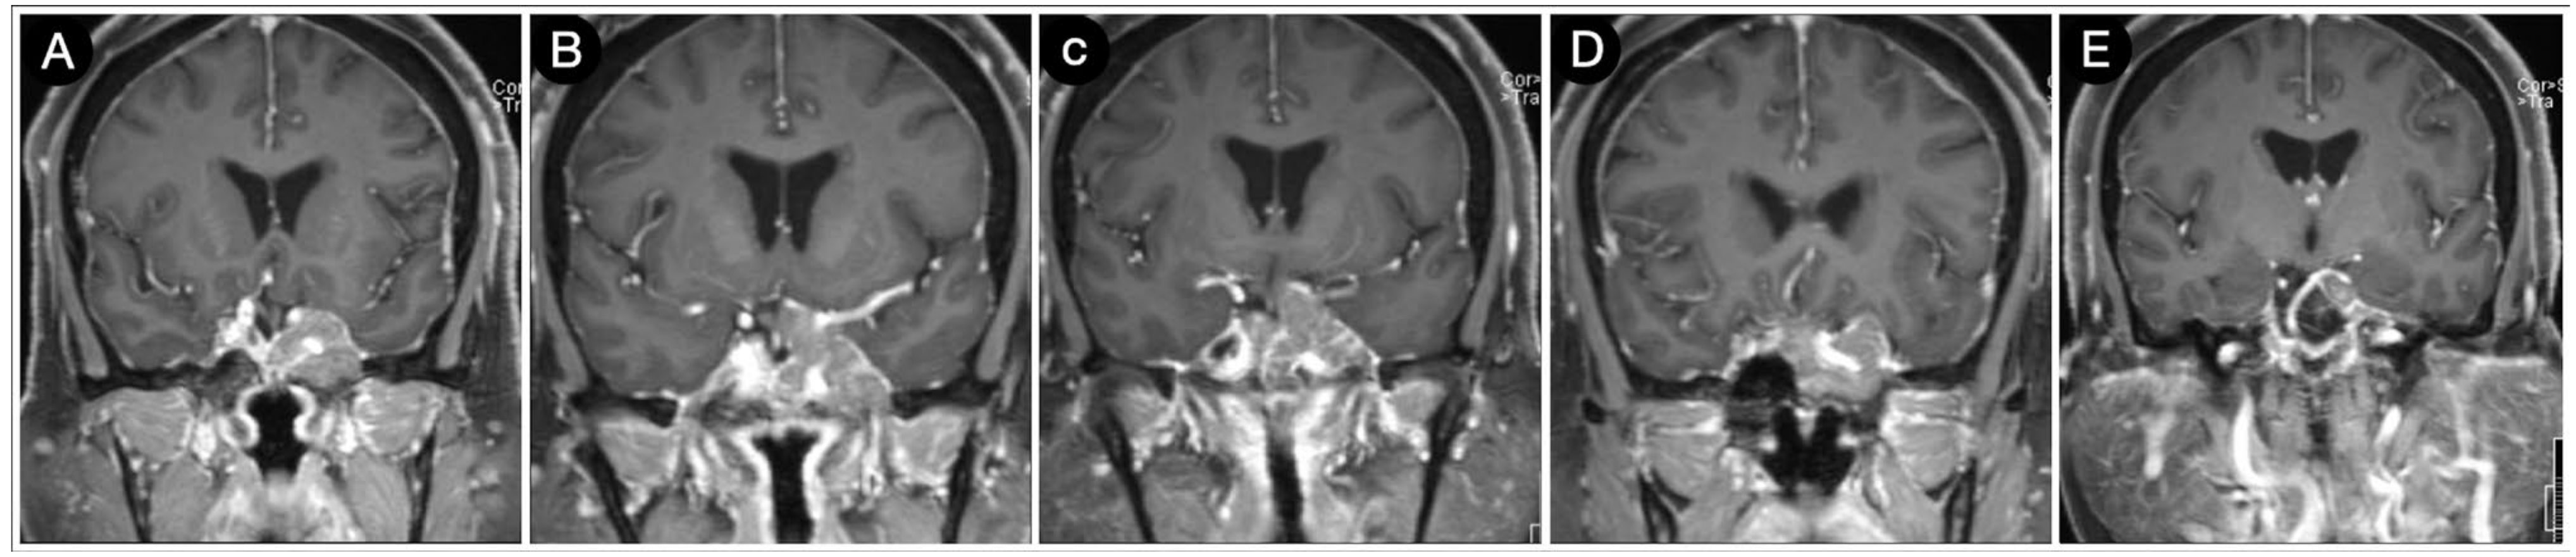

Case #1: Infradiaphragmantic Tumor with Middle Fossa Involvement through the Cavernous Sinus